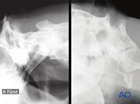

C1 (Atlas) fractures